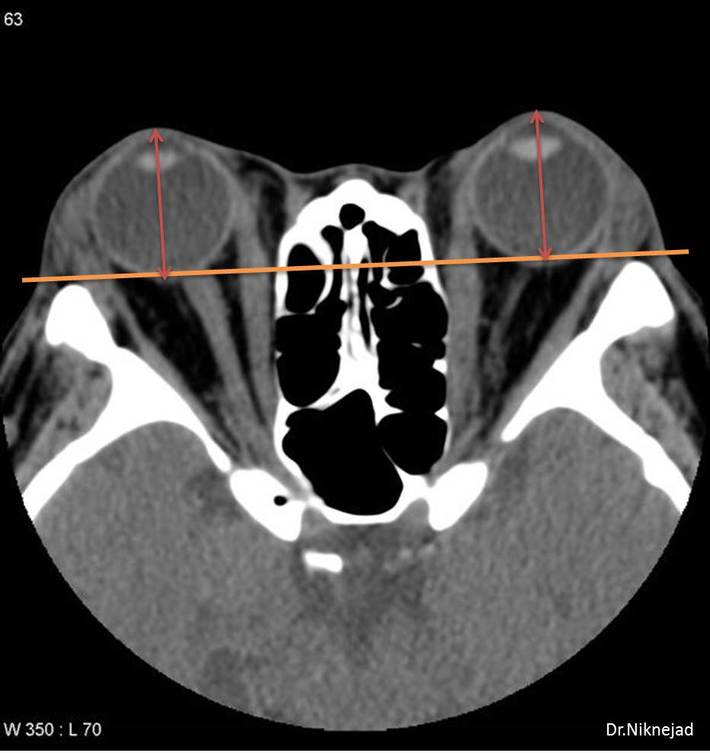

What is the diagnosis?